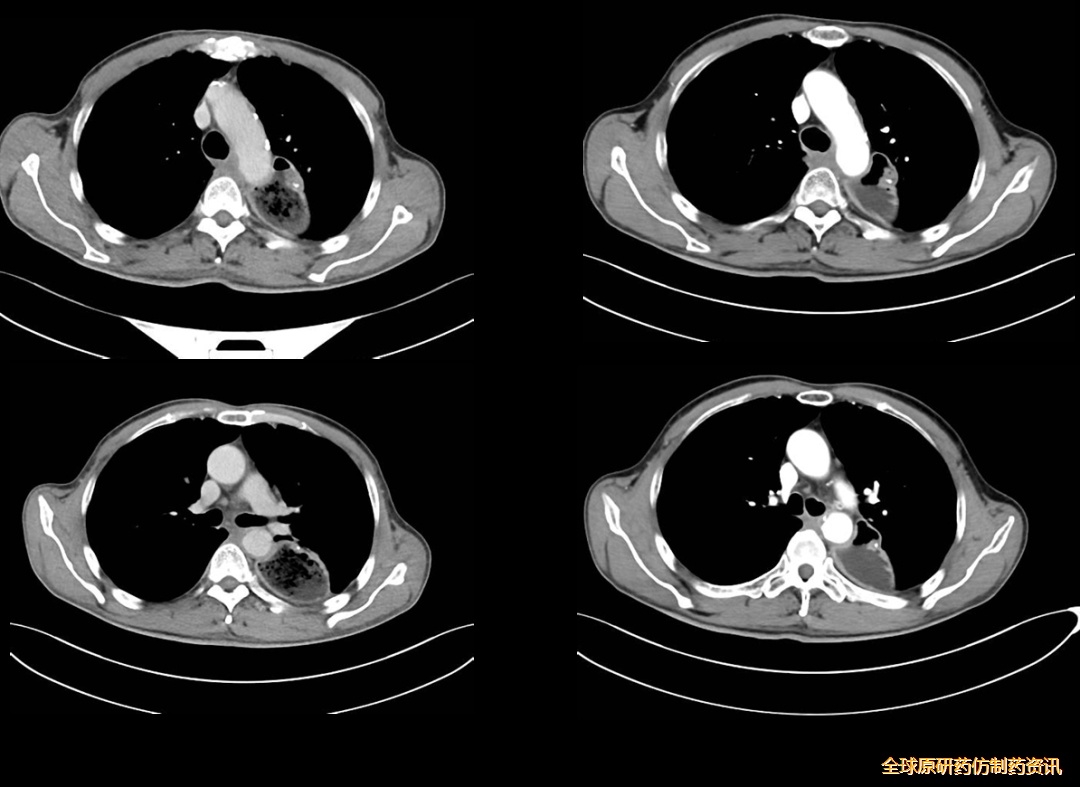

图4 影像学检查结果对比

疗效评估:PR

图5 影像学检查结果对比

免疫维持期间疗效评估:SD